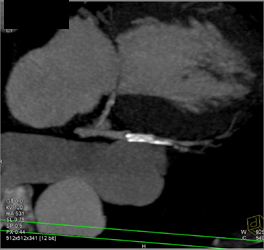

Diagnosis

Patent LAD Stent